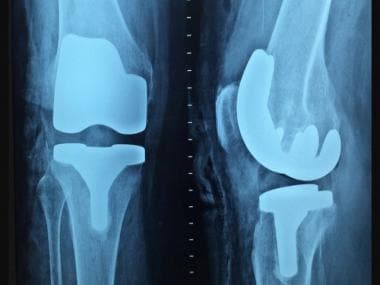

Representational Image. credit: PxHere